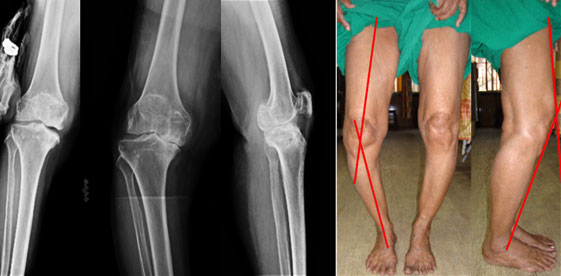

70 year old lady, presents with pain in both the knees right more than left, difficulty in walking, bowing of both legs. The x-rays show osteoarthritis of knee joint, destruction of joint cartilage, varus deformity. The pictures on the right show the clinical appearance. When looking from the front there was severe bowing of the legs and on looking from the side there was flexion deformity (knees bent). Both the deformities adding mechanical disadvantage to the destroyed joint cartilage.